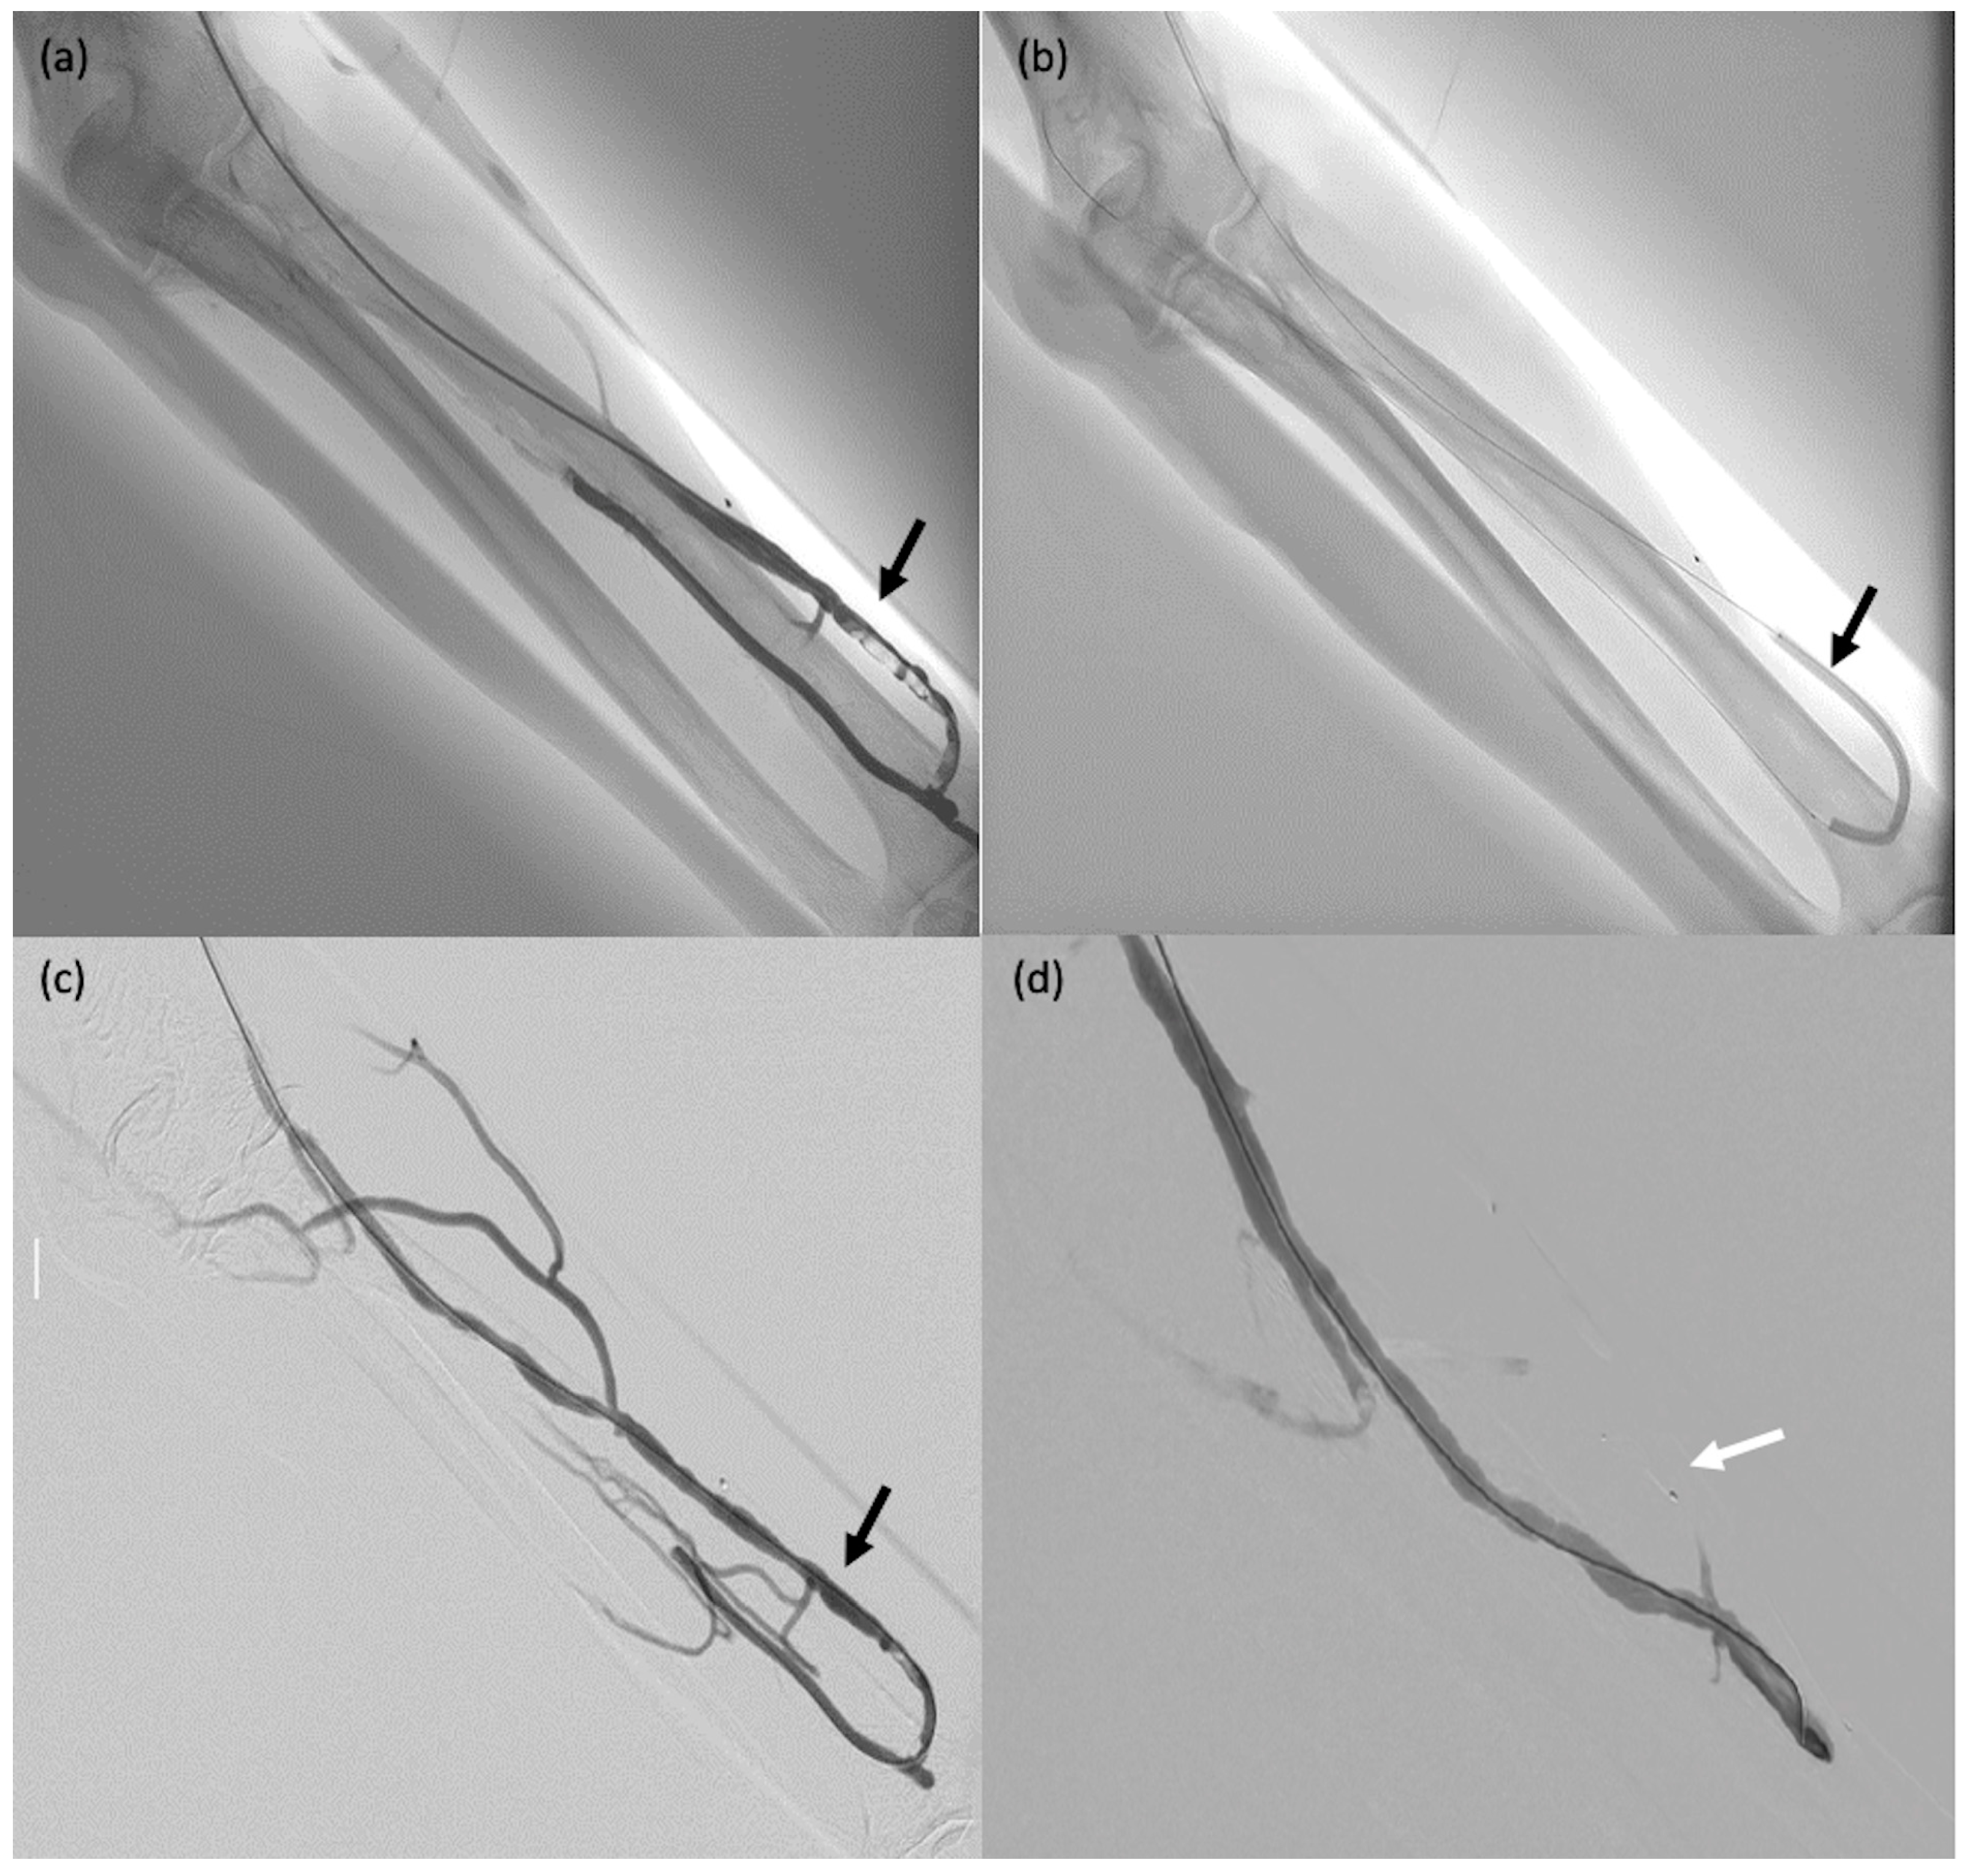

Figure 4. A 75-year-old male patient (#29) on dialysis for chronic kidney disease with dysfunction of the arteriovenous fistula. (a) Post-anastomosis venous thrombosis (arrow): the patient was taken to the operating room for thrombectomy. (b,c) Thromboaspiration and angioplasty (arrows). (d) MVP-5Q implantation to occlude collateral venous circulation, thereby redistributing the blood flow (arrow).